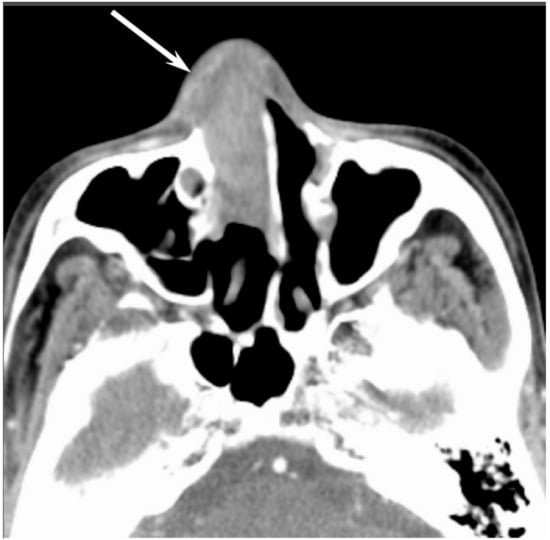

Figure 4. Sinonasal undifferentiated carcinoma of the right nasal cavity. Contrast-enhanced CT image showing an ill-demarcated, heterogeneously enhanced lesion (arrow).

Most SNUCs are larger than 4 cm in maximal diameter at presentation and have ill-defined margins [23]. The aggressive nature of the tumor is reflected in the bone destruction and invasion of adjacent structures, including the paranasal sinuses, anterior fossa, orbit, pterygopalatine fossa, parapharyngeal space, and cavernous sinus [23]. On CT, SNUCs usually appear as a noncalcified mass and show variable contrast enhancement and areas of central necrosis. On MRI, SNUCs show isointensity on T1WI, iso- to hyperintensity on T2WI, and exhibit heterogeneous enhancement on contrast-enhanced T1WI. Owing to the nonspecific imaging findings, it is typically difficult to distinguish between SNUCs and SCCs (Figure 4).